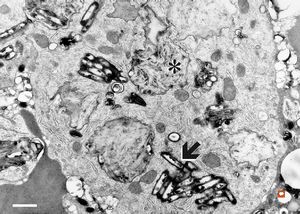

Whipple disease